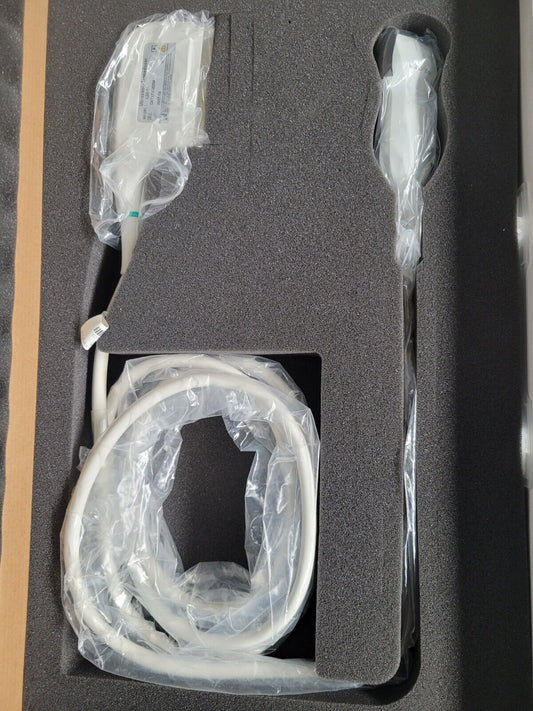

Mindray L14-6Ns Linear Ultrasound Transducer Probe (New)

Regular price $1,999.00 USDRegular priceUnit price / per -

Mindray L14-6Ns Linear Ultrasound Transducer Probe (New)

Regular price $2,499.00 USDRegular priceUnit price / per -